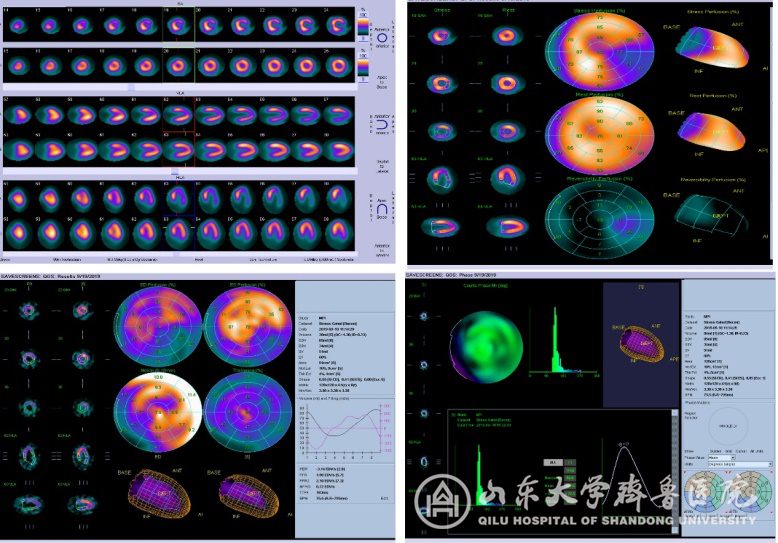

在早期诊断冠心病心肌缺血、评价心肌储备功能、估测冠心病患者受累血管供应区域心肌缺血范围与程度、评价心肌梗死、冠脉搭桥术术前病例选择及术后疗效评估及冠心病治疗后疗效观察等方面均具有重要意义。此外,这是唯一能评价单侧肾功能的检查方法,新机器进一步根据病人的身高体重进行修正,可以获得更加精确的“标准化”肾小球滤过率值(Normalized GFR)。